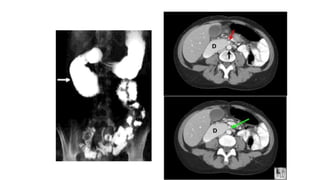

• Diagnosis may follow X-ray examination revealing duodenal

dilation followed by abrupt constriction proximal to the

overlying SMA.

• Standard diagnostic exams include abdominal and

pelvic computed tomography (CT) scan with oral and IV

contrast, upper gastrointestinal series (UGI), and, for equivocal

cases, hypotonic duodenography.

• Criteria in CT scan : is aortomesenteric angle of less than 22

degree and distance of less 10-8 mm. In children, an angle of

less 20 degree.

Diagnosis • Is verydifficult, and usually one of exclusion. • Diagnosis may follow X-ray examination revealing duodenal dilation followed by abrupt constriction proximal to the overlying SMA. • Standard diagnostic exams include abdominal and pelvic computed tomography (CT) scan with oral and IV contrast, upper gastrointestinal series (UGI), and, for equivocal cases, hypotonic duodenography. • Criteria in CT scan : is aortomesenteric angle of less than 22 degree and distance of less 10-8 mm. In children, an angle of less 20 degree. • The reason for the persistence of gastrointestinal symptoms